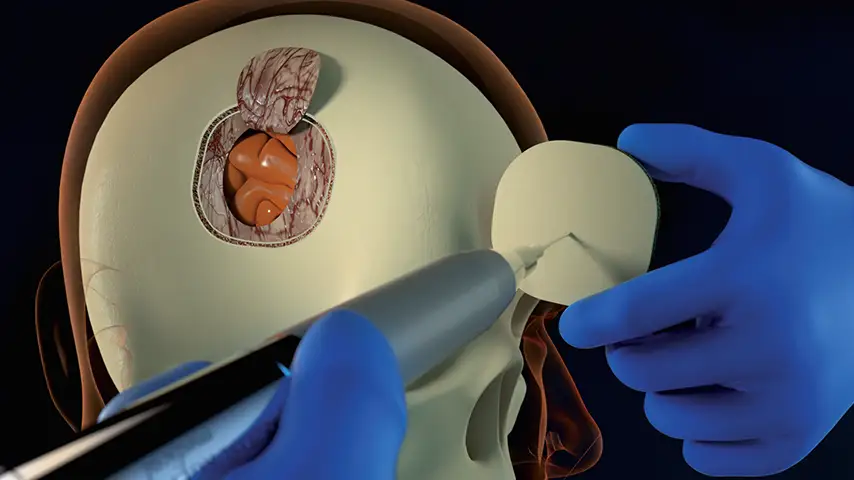

Cranioplasty

and reshaping of frontoorbital bandeau

Selective cut preserves soft tissue. (Dura, neves and vessels)

Exeptional precision and versatility in bone remodeling

Micrometric cut for minimal bone loss

Reduced need for fixation and graft materials

Post-operative Benefits

ENHANCED HEALING

Improved recovery and faster bone healing.

REDUCED RISK OF EDEMA

Postoperative swelling and discomfort.

REDUCTION OF COMPLICATIONS

Minor risk of recurrences.